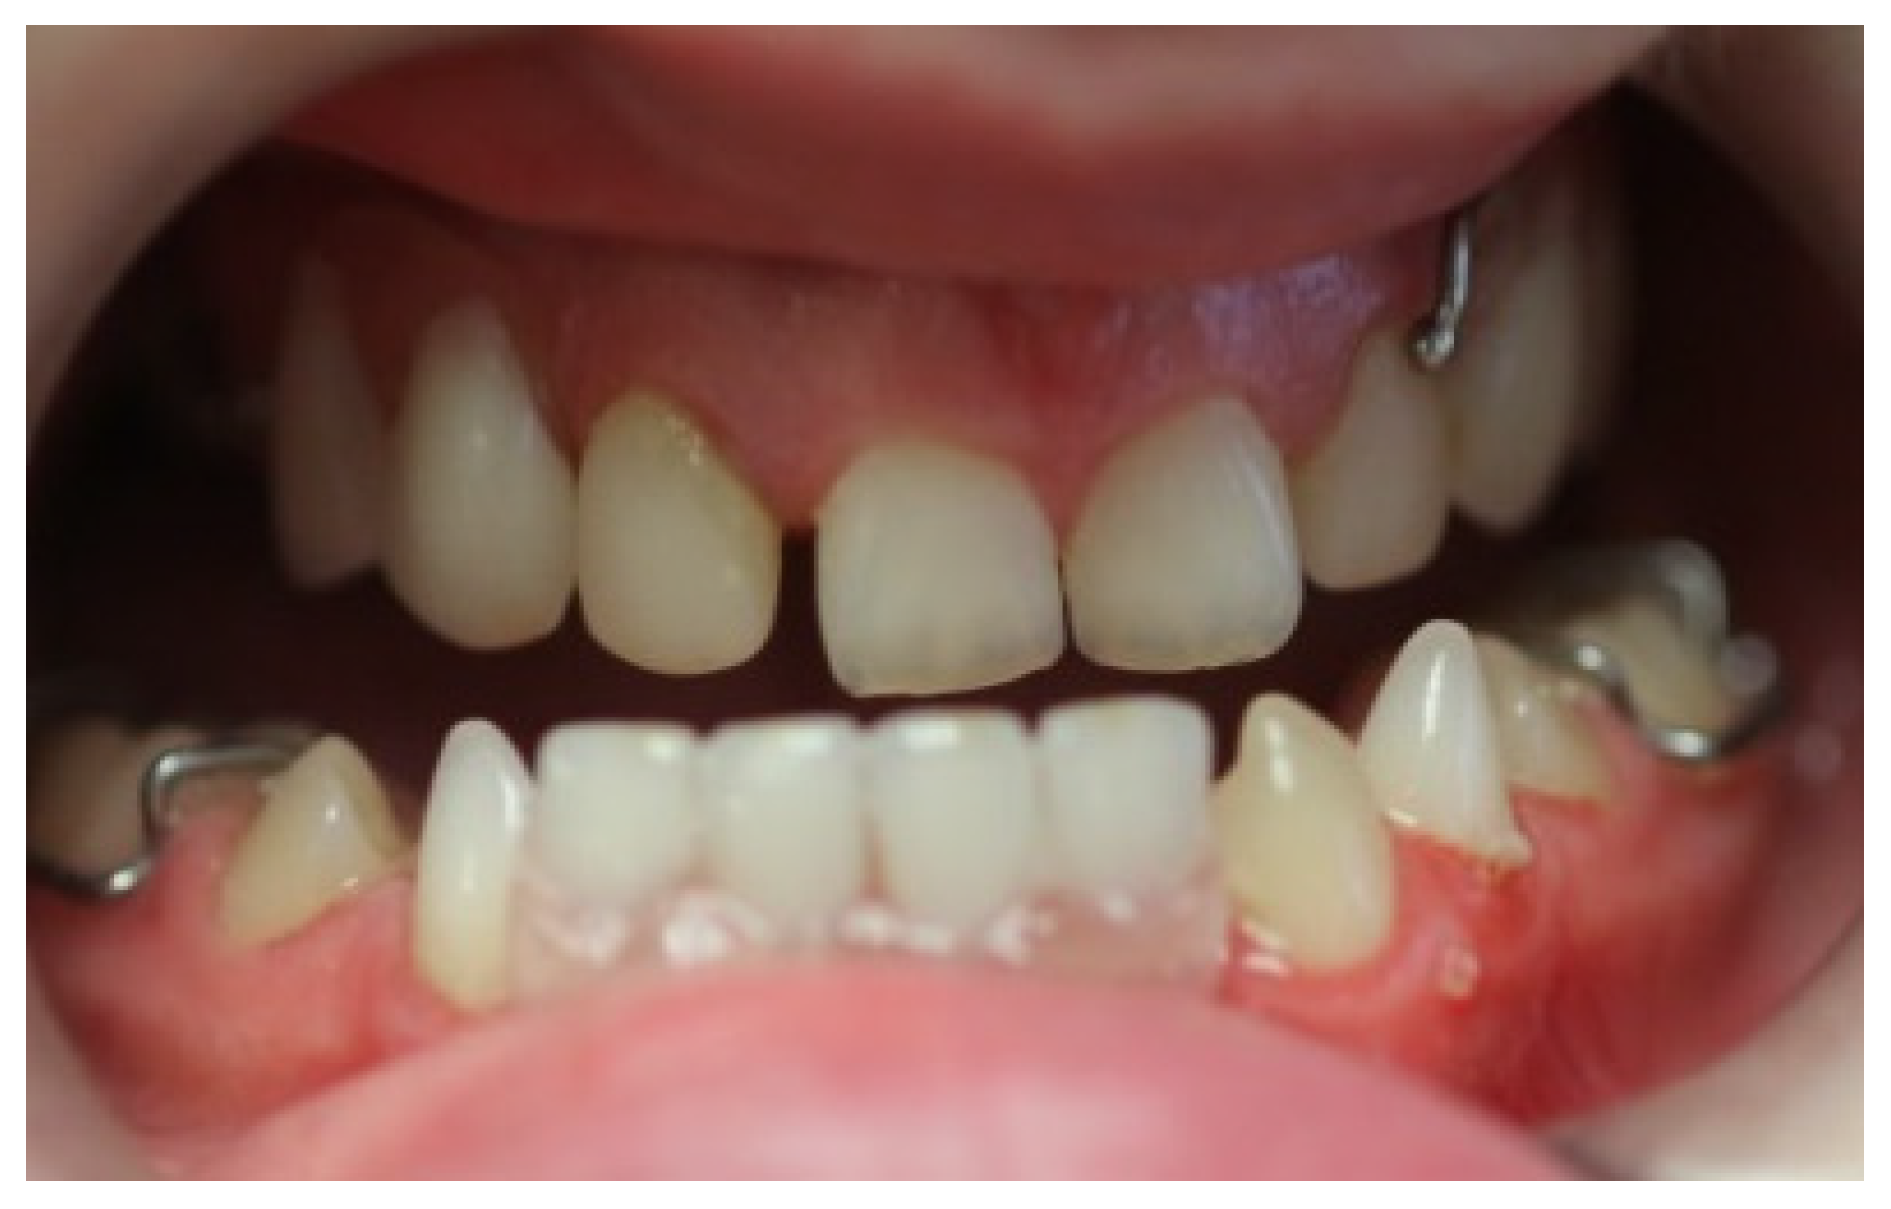

Artificial teeth (VITAPAN, Vita, Zurich, Switzerland) were arranged and processed using heat-polymerized acrylic resin (Lucitone 199, Dentsply International, York, PA, USA). A laboratory remount procedure was performed to refine the occlusion before final polishing. The extraction of teeth 72, 81, and 82 was performed and hemostasis was achieved. At the insertion of the upper and lower dentures, pressure-indicating paste (PIP, Mizzy, Keystone Industries. GmbH, Germany) was used to assess fit with the necessary adjustments completed chairside (Figure 5).

Figure 5. Intra-oral photograph after placement of upper overdenture and lower immediate denture.